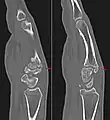

Carpal boss in plain X-Ray.